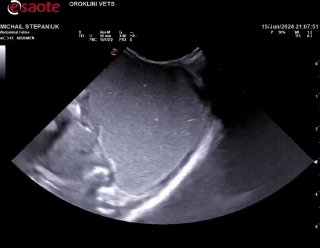

Нарушена перистальтика скорее всего, дело не в Кале, молоко не переходит из желудка дальше, а выходит обратно… надо узи. В ороклини пообещали принять, но уже 6:30, с 2 жду((( никто не пришел туда

Заворот желудка тоже может быть. На практике был один малыш,ему было пара недель вроде,заворот,оперировали и удачно,вырос в большого котэ🐈